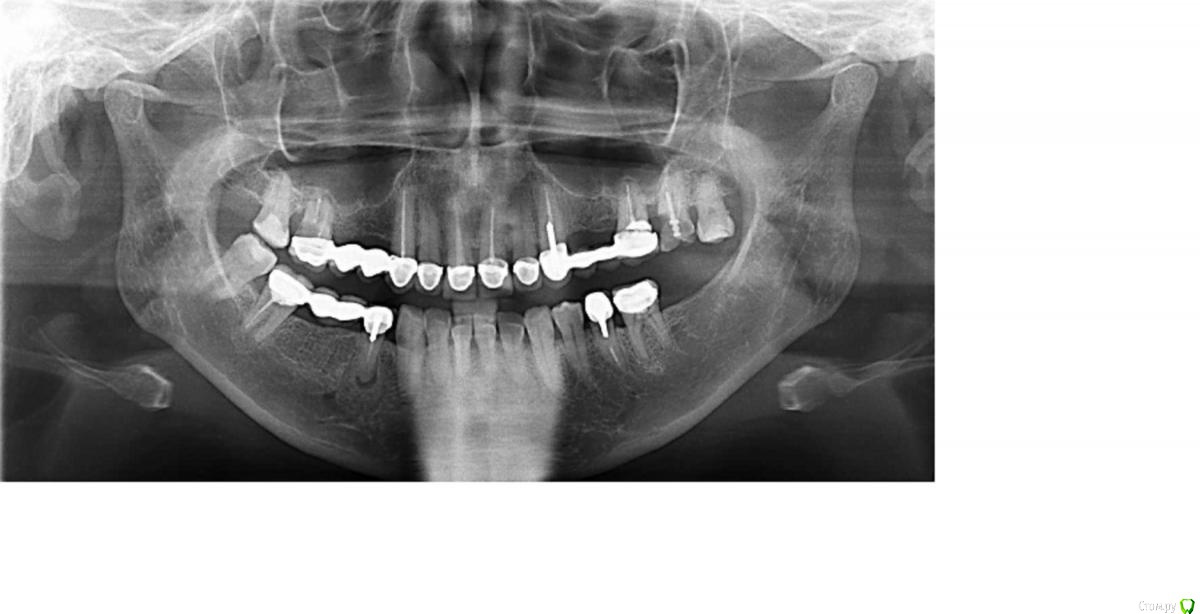

Ленусик333 Опубликовано 2 августа, 2016 Автор Поделиться Опубликовано 2 августа, 2016 Снимок от 02.08: Ссылка на комментарий

DmitrySH Опубликовано 2 августа, 2016 Поделиться Опубликовано 2 августа, 2016 ....а пролечить все перед ортопедией 1 Ссылка на комментарий

krokomot Опубликовано 2 августа, 2016 Поделиться Опубликовано 2 августа, 2016 Это постоянные конструкции? если да то печаль Ссылка на комментарий

Ленусик333 Опубликовано 3 августа, 2016 Автор Поделиться Опубликовано 3 августа, 2016 Спасибо всем, кто отвечает.Да, это постоянные конструкции, уже прошедшие полную "подгонку", но пока они стоят на временном цементе. Так как меня мало устраивает внешний вид верхнего зубного ряда, а также я планирую заняться лечением десны (сильно ушедшей "вверх), то я попросила доктора поставить пока все на временный.Могу я попросить вас конкретизировать, что не так с лечением? Все зубы перед ортопедией мне пролечили.Также для меня важен вопрос: видна ли на рентгене ДО и ПОСЛЕ разница в состоянии десневой ткани сверху? В клинике отрицают факт изменения десны по их вине, хотя это произошло в процессе протезирования и по этому поводу мне собственно переделывали уже готовые коронки.Спасибо всем.Еще раз поставлю рентген до и после: Ссылка на комментарий

DmitrySH Опубликовано 3 августа, 2016 Поделиться Опубликовано 3 августа, 2016 Могу я попросить вас конкретизировать, что не так с лечением? Все зубы перед ортопедией мне пролечили. На данных снимках нет возможности оценить состояние мягких тканей. А состояние зубов до и после осталось одинаковымНужна ревизия каналов зубов :17, 16, 26, 27, 44, 47. состояние зубов 16, 27 ( на основании снимка) вызывает сомнения в их сохранении. 4 Ссылка на комментарий

red_butler Опубликовано 3 августа, 2016 Поделиться Опубликовано 3 августа, 2016 если не заняться полостью рта комплексно, в ближайшее время сосочки покажутся мелочью. 2 Ссылка на комментарий

DmitrySH Опубликовано 3 августа, 2016 Поделиться Опубликовано 3 августа, 2016 В этих мостовидных конструкциях есть очень большой плюс. Можно спокойно разбираться с зубами на верхней челюсти. Произвести имплантацию в области 24,25, 14,15.И при всех этих манипуляциях пациентка будет с зубами, сможет комфортно питаться и общаться. Ссылка на комментарий